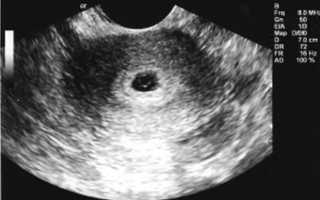

Именно по такому состоянию эндометрия удается диагностировать беременность на очень ранних сроках, то есть тогда, когда плодное яйцо еще не видно. Также этот показатель влияет на диагностику самопроизвольного аборта (выкидыша) на очень ранних сроках. Иногда женщина может такого выкидыша не заметить или не почувствовать, и тогда УЗИ, в ходе которого диагностируются изменения, подтверждает сам факт наличия беременности несколько дней назад.

- Ультразвуковое исследование, на котором визуализируются толщина и структура эндометрия;